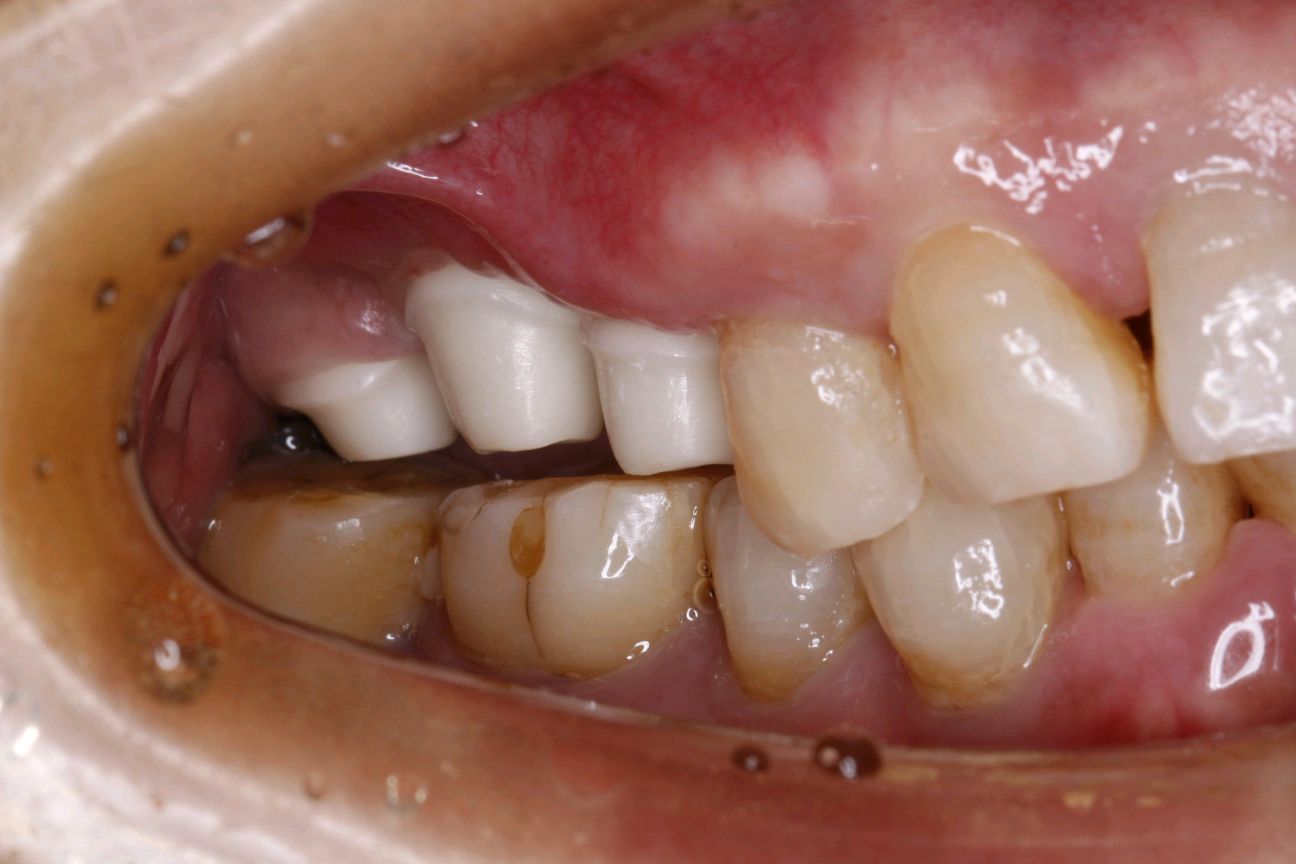

患者女,65 岁。右上 6、7 已做过两颗种植牙,因右上 5 松动,影响咀嚼,要求治疗。 口腔检查:右上 67 种植牙存,右上 5 叩诊+,探诊深牙周袋,冷热无反应,龈周-。X 线示 根尖周大面积阴影,颌面可见近远中折裂。诊断慢性根尖炎,牙根折裂。无法保留,建议拔除后,种植修复。

术前